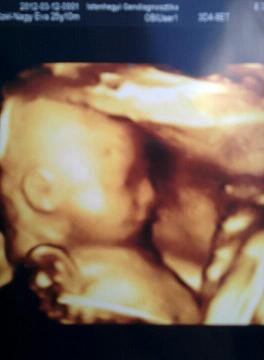

Voltunk 4d-n, olyan szép ez a kölök 8) :)

Nyuszuli: Nincs kedved megosztani velünk a 4D-s képet? :D

Zafír! De, szivesen felteszem a képeket :)

Kép

a többi még nincs gépen, ez is telefonnal gyorsan :)

Szép kerek már a pocid :) Az uh-s kép nagyon aranyos :)